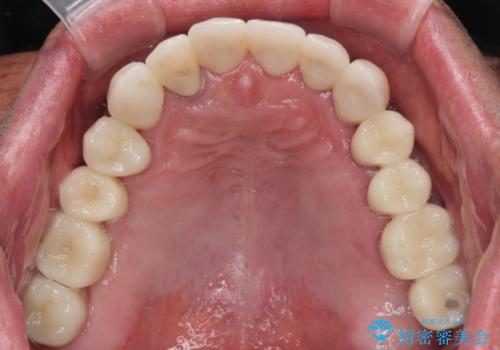

欠損部はインプラントによる補綴治療を行うこととし、臼歯部が安定した後に、上下前歯部をオールセラミッククラウンにて補綴治療を行うこととしました。

上顎前歯に歯周ポケットの深い部分がありましたが、インプラントの仮歯で奥歯がしっかりと噛めるようになると、1年程度で深い歯周ポケットは解消されました。

前歯部の審美面も大幅に改善され、大変満足していただけました。